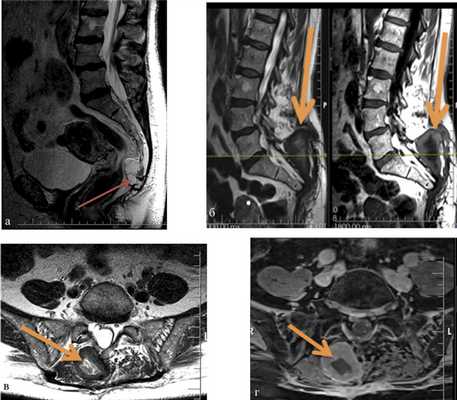

В нашей серии гнойные осложнения наблюдались у 10 (27%) пациентов, из них у 6 было глубокое нагноение раны. В случаях подтвержденного глубокого нагноения проводилась ревизия операционной раны с последующим дренированием и установкой приточно-отточной системы. В 1 случае потребовалось открытое ведение раны с аспирационной повязкой. У 1 пациентки наблюдалось нагноение межмышечной гематомы (рис. 2). Рис. 2. МРТ крестца и таза у пациентки с хордомой крестца. а — до операции, сагиттальная проекция, опухоль указана стрелкой; б—г — после операции, сагиттальная (б) и аксиальная проекции (в, г). Нагноившаяся гематома указана стрелкой.